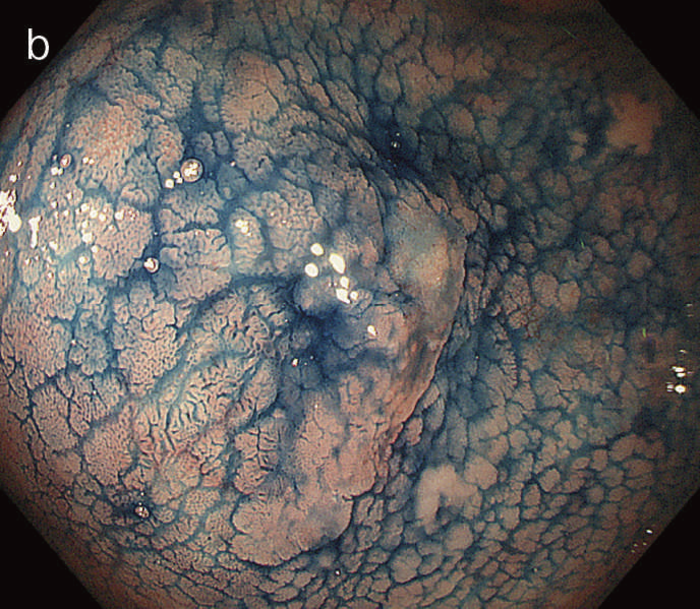

図6 UC関連LGDの内視鏡所見

- 白色光像:直腸(下部直腸)に色調変化は乏しく,微小な隆起を複数認めた。背景粘膜は寛解期にあった。

- NBI非拡大像:Brownishな領域が明らかとなった。

- 色素内視鏡像:病変辺縁が明瞭な微小な隆起を複数伴う表面平坦型病変。

- NBI拡大像:口径整でらせん状の微小血管と絨毛状の表面構造を認めた。

- pit pattern像:小型の類円形,管状pitを認めた。